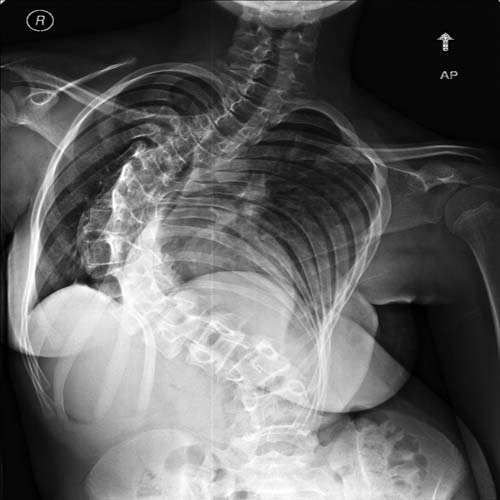

نجح فريق طبي بالمستشفى السعودي الألماني بالرياض، في إجراء جراحة دقيقة لإصلاح اعوجاج شديد بالعمود الفقري لفتاة سعودية تبلغ من العمر 14 عاما تعاني من اعوجاج شديد بالعمود الفقري.

وكانت المريضة قد حضرت للمستشفى وهي تعاني من اعوجاج شديد بالعمود الفقري، وبعد عمل الفحوصات اللازمة أجريت لها عملية جراحية دقيقة، حيث تم قص عظمي لفقرات العمود الفقري على مستويات متعددة، ثم تثبيت للفقرات بواسطة مسامير عنق الفقرة وأعمدة من الخلف مع عمل التحام للفقرات، مما أدى إلى تحسن شكل العمود الفقري بعد هذه الجراحة الدقيقة. وبفضل الله تماثلت المريضة للشفاء وهي الآن في فترة النقاهة.